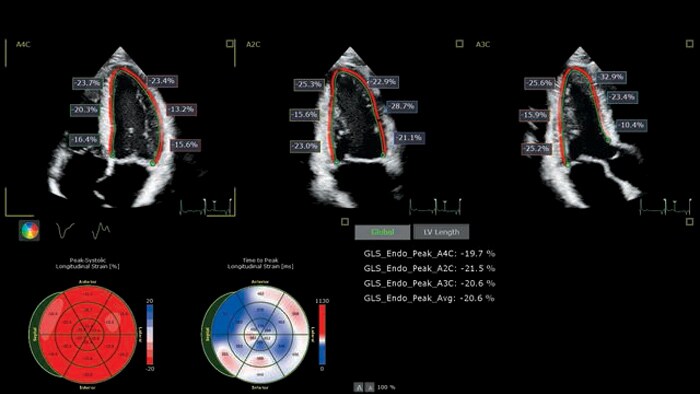

Вы не найдете аналогов. Уникальный, быстрый и удобный анализ AutoStrain использует усовершенствованную технологию визуализации для получения достоверных и воспроизводимых результатов измерений окрашенных структур.

Д-р Тереза Лопез Фернандез (Teresa Lopez-Fernandez), La Paz University Hospital, г. Мадрид, Испания

Использование передовых инструментов для ультразвукового исследования при сердечной недостаточности на фоне лечения рака (CTRCD)

Затратные по времени методы уходят в прошлое благодаря применению инструмента Philips Anatomically Intelligent Ultrasound (AIUS) для предотвращения негативного влияния противоопухолевой терапии на сердце.